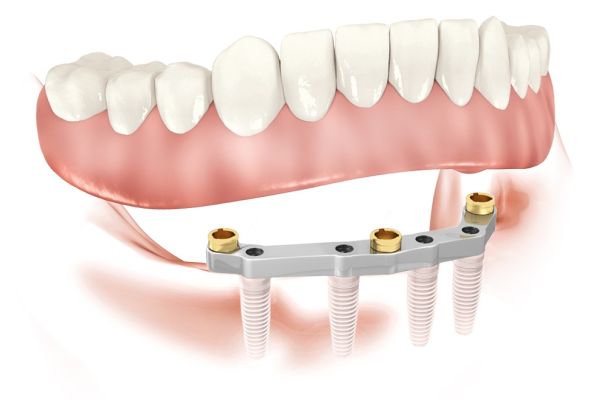

Пошаговое руководство по установке съёмного протеза на импланты